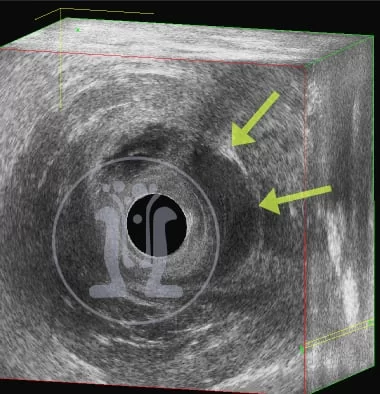

24 09 2018 Το συριγγιο ήταν διπλό

Εγινε παραπομπή ασθενούς από άλλο συνάδελφο για χαρτογραφηση του συριγγίου. Κατά την εξεταση διαπιστώθηκε ότι υπήρχαν δυο συριγγια στην 6η … Περισσότερα